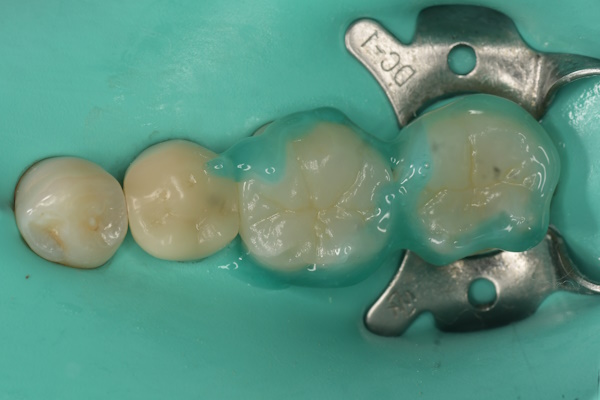

セラミック治療の治療例です。歯科治療に対する強い恐怖心があり、これまで継続的な通院が難しい状態でした。臼歯部には過去の治療歴があり、詰め物の下から虫歯が再発している状態(二次カリエス)が認められました。当院にて、患者様の不安を軽減するため静脈内鎮静法を併用し、2本同時に虫歯を除去したうえで、同日にセラミックによる修復を実施しました。接着効率を高めるため、ラバーダムを使用しています。オキシガードは、過酸化物と還元剤による化学重合反応により、歯科接着用レジンセメント表面の未重合層を硬化させる材料です。さらに、未重合層を空気から遮断することで、確実な硬化を促します。

オキシガード使用後